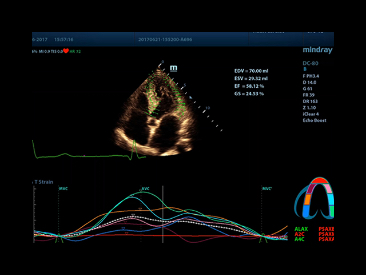

TT QA

Track myocardial motion by detection of the 2D speckle patterns, provide LV regional abnormalities diagnostic information.